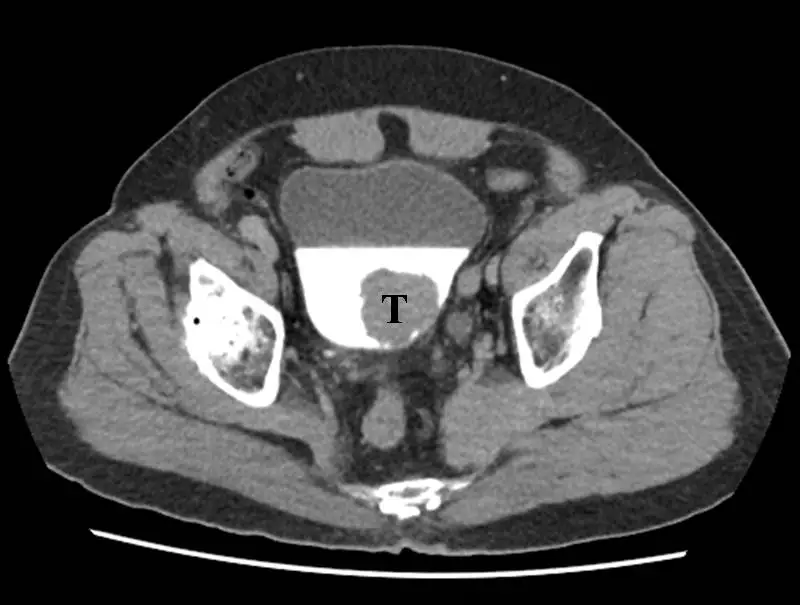

圖例 為⼀病患之電腦斷層影像,下列敘述何者正確? ①影像中膀胱含有對比劑,標⽰ T處為疑似腫瘤 ②此為腹部切⾯,中央的胃中含有對比劑,標⽰ T處疑似腫瘤 ③電腦斷層掃描使⽤的對比劑為含碘物質 ④病⼈在注射對比劑後,必須等待⾄延遲相( delayed phase )才能得到此影像

圖中顯示一張骨盆腔(pelvis)橫切面(axial plane)CT 影像,特徵如下:

- 整體解剖定位:影像中央可見骨盆腔結構,兩側為髂骨(ilium)(呈高密度白色皮質骨),後方可見薦骨(sacrum)

- 中央高密度結構:正中央可見一個大面積高密度(亮白色)充填的空腔狀結構,與周圍軟組織對比鮮明,符合**含對比劑的膀胱(urinary bladder)**特徵。對比劑為含碘物質,在 CT 影像中呈高密度

- T 標記:「T」位於膀胱內,指向膀胱腔內一個中等密度的充填缺損(filling defect)或軟組織腫塊,提示為膀胱腫瘤(bladder tumor),其密度低於周圍的含碘對比劑

- 無胃的可見結構:此切面高度(骨盆腔層級)遠低於腹腔,胃不會出現在此切面;影像中無任何胃的特徵(胃在上腹部,位於橫膈以下、肚臍以上)

影像判讀結論:此為骨盆腔切面,中央亮白結構為含對比劑的膀胱,T 處為膀胱內疑似腫瘤,而非胃。